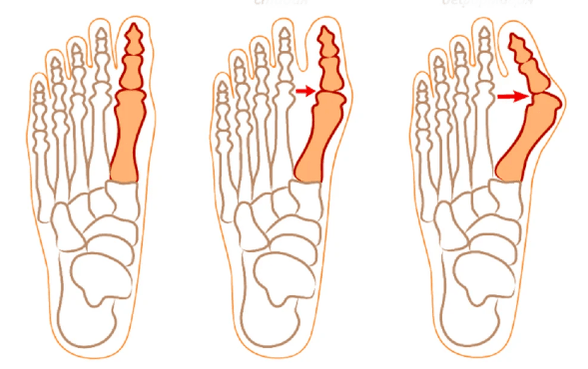

Doctors consider 3 stages of disease progression:

Complete healing of hallux valgus is possible only with the help of a surgeon's scalpel.Sometimes only one operation is enough and the patient forgets about the problem forever.The doctor performs the surgical intervention taking into account the type of hallux valgus deformity.The most common types of operations are:

- Exotectomy.Only a certain part of the metatarsal bone is removed.

- Resection arthroplasty.The end of the metatarsal bone is removed.

- Osteotomy.It is used to remove the metatarsal bone, as well as a small element of the phalanx.

- Distal osteotomy.The operation involves reducing the angle between the joints.